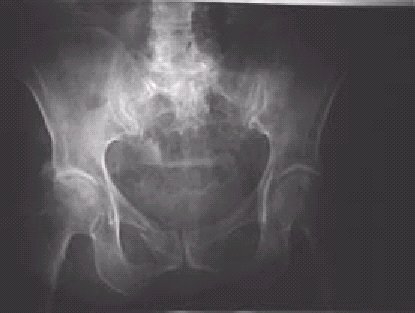

—Fractura de ramas iliopubiana e ilioisquiática derechas. La fractura unilateral de ambas ramas púbicas es uno de los tipos más frecuentes de fractura pélvica.